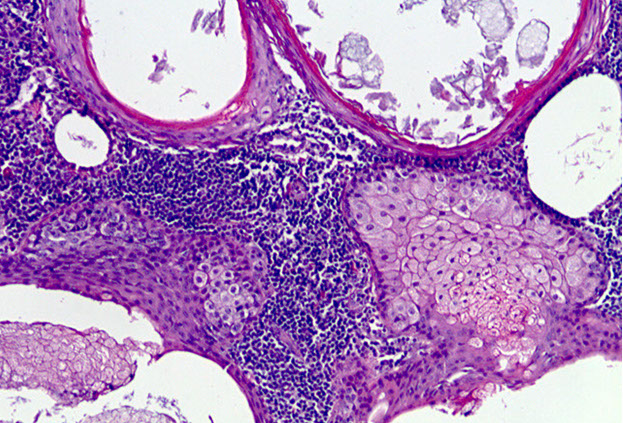

Adenomatoid Odontogenic Tumor (AOT)

- aka adenoameloblastoma

Odontogenic tumor arising from enamel organ or dental lamina

- rare; seen in younger pts, 2F>1M; usually in anterior maxilla, and most are assoc c an impacted canine tooth

Imaging: radiolucency around an unerupted tooth extending past the cementoenamel junction

- usually has faint flecks of radiopacities surrounded by radiolucent zone

Gross: crown of tooth usually projects into cystic cavity

Micro: well-circ, central prolif of duct-like epithelium surrounded by small foci of calcification

- may see rosettes, trabecular or cribriform patterns of epithelium

- columnar-type cells c basal nuclei and clear cytoplasm can looklike pre-ameloblasts

- eosinophilic material seen in bwt tumor cells and in ductlike structures

Tx: enucleation

AOT c fibrous connective tissue capsule (*), nodular aggs of cells (#), and duct-like strucures (->)

Gland-like spaces surrounded by cuboidal to columnar cells (->)

AOT